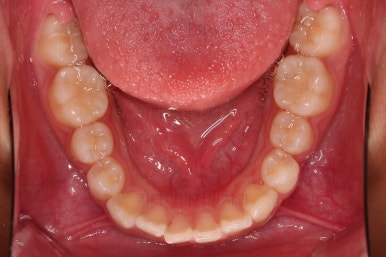

부산소아교정 마무리 사진입니다.

프리올소로 유지과정까지 총 2년 3개월 가량 걸렸고요.

이정도 마무리면 굳이 2차교정까지 안해도 되겠죠?

정교한 조절은 안했지만 치열이나 교합/맞물림 등 매우 좋아졌습니다.